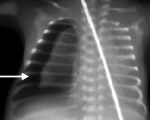

• Рентгенография ОГК. На рентгенограмме неонатолог определяет засветку периферических отделов грудной клетки и коллапс (коллапс) легкого. При этом средостение, как правило, смещается в здоровую сторону. Рентген также используется для диагностики пневмоперикарда.